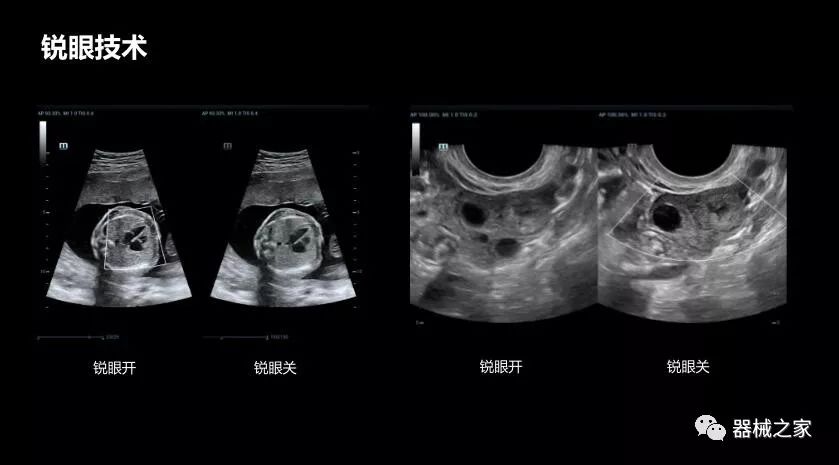

• 銳眼技術(shù)

做胎兒心臟檢查的時(shí)候,如果是聲窗不好的孕婦,很難看清胎兒心腔 。女媧Resona 8的銳眼技術(shù)能很好的優(yōu)化心腔內(nèi)的噪聲,讓胎心結(jié)構(gòu)完美的呈現(xiàn)。